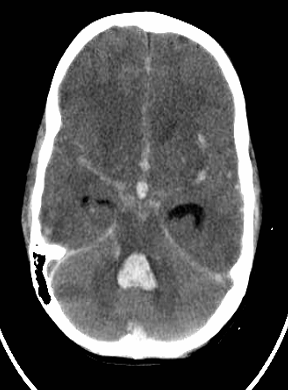

Subarachnoid and intraventricular hemorrhage

blood in 3rd and 4th ventricles hyperintense - (((with compression of lateral ventricular temporal horns

Noncontrast CT of the head (axial section)